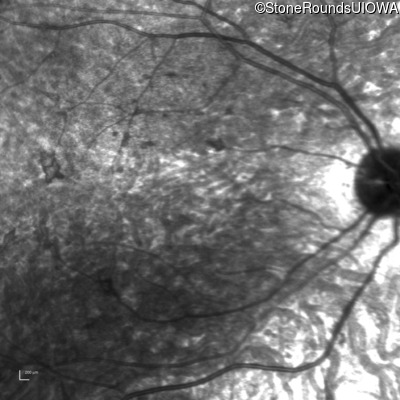

Age at visit: 8 years

OD OS

This 8 year old girl had normal vision until age 6 when she failed a school vision screening. That year, she was able to play softball well, but this year she often loses sight of the ball and is often hit by it.